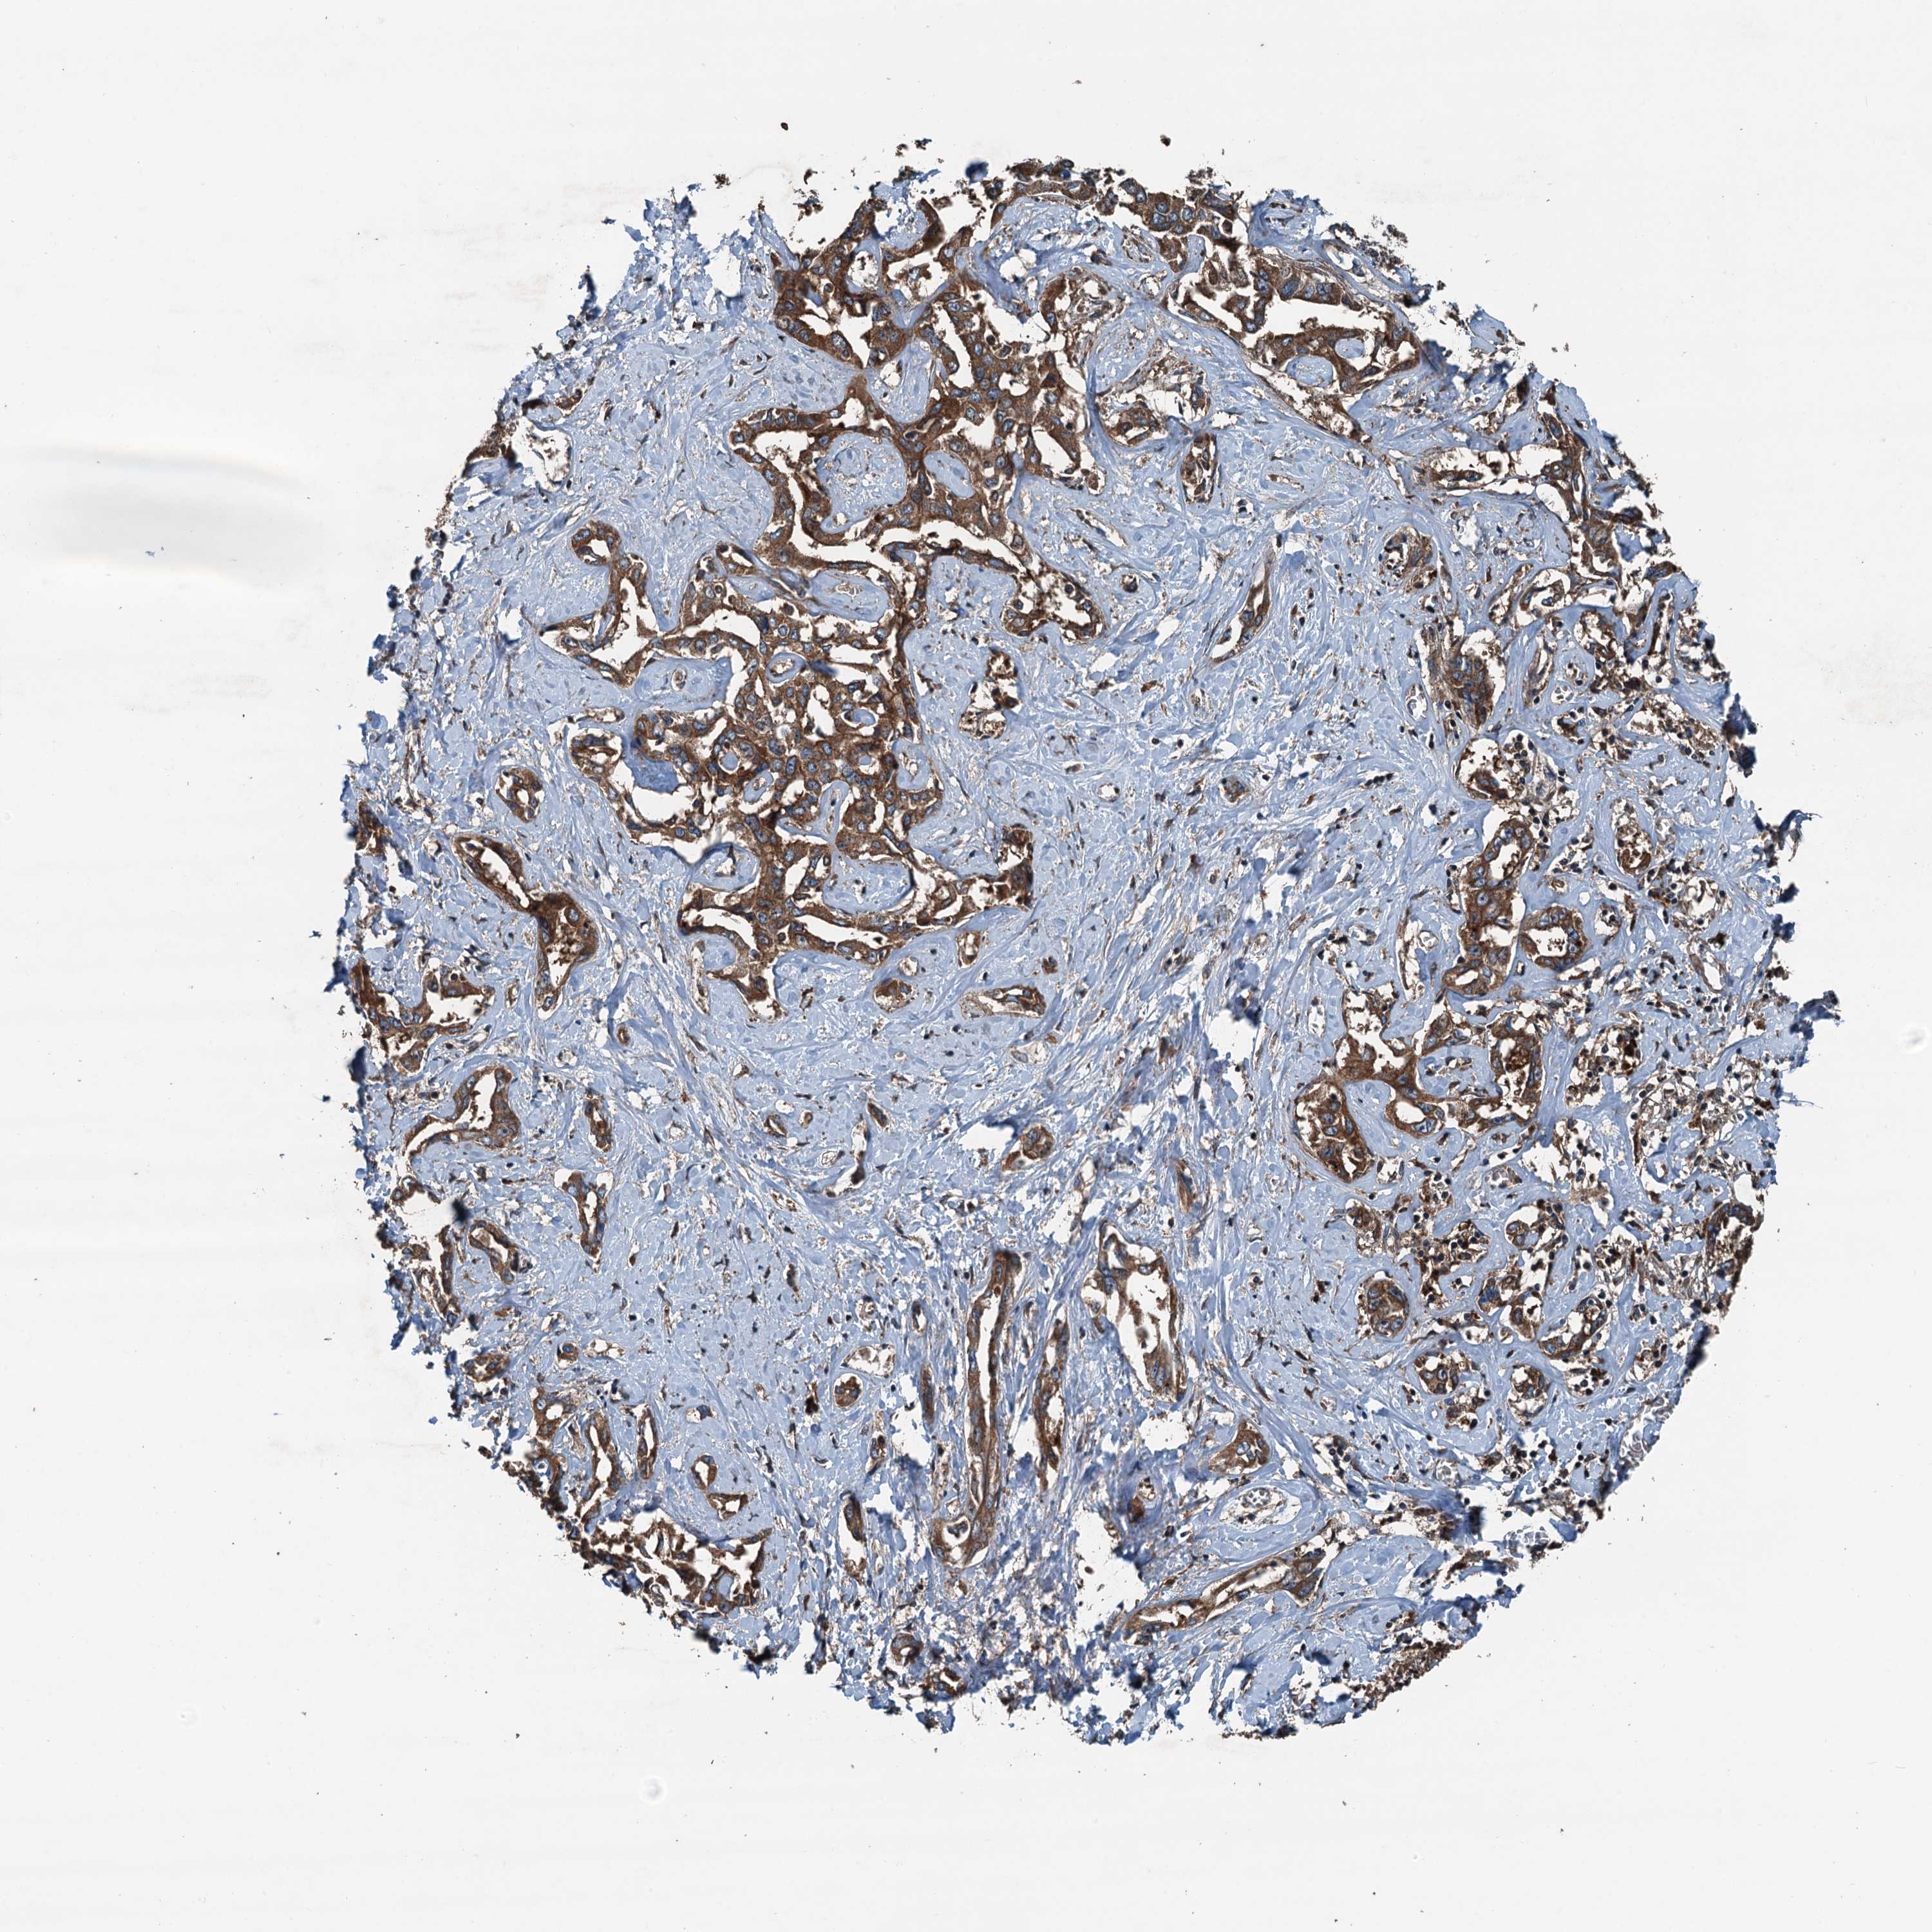

LIVER CANCER - Protein expressioni

A mouse-over function shows sample information and annotation data. Click on an image to view it in a full screen mode. Samples can be filtered based on level of antibody staining by selecting one or several of the following categories: high, medium, low and not detected. The assay and annotation is described here.

Note that samples used for immunohistochemistry by the Human Protein Atlas do not correspond to samples in the TCGA dataset.

Antibody stainingi

Antibody staining in the annotated cell types in the current human tissue is reported as not detected, low, medium, or high, based on conventional immunohistochemistry profiling in selected tissues. This score is based on the combination of the staining intensity and fraction of stained cells.

Each image is clickable and will lead to virtual microscopy that enables deeper exploration of all samples and also displays staining intensity scores, fraction scores and subcellular localization as well as patient and tissue information for each sample.

Antibody HPA041227

Staining

High

Medium

Low

Not detected

Intensity

Strong

Moderate

Weak

Negative

Quantity

>75%

75%-25%

<25%

None

Location

Nuclear

Cytoplasmic/membranous

Cytoplasmic/membranous,nuclear

Cholangiocarcinoma

Carcinoma, Hepatocellular, NOS